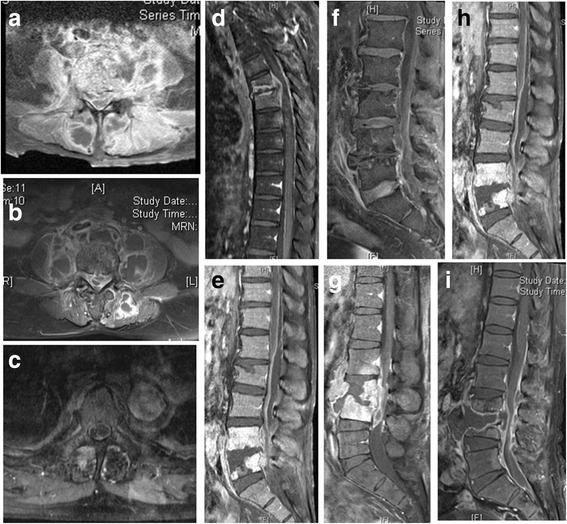

Compared with 37 GPC-HPS patients, the 17 GNB-HPS patients were more often found to be older individuals, a history of cancer, and a previous history of symptomatic urinary tract infection. They also had a less incidence of epidural abscess formation compared with GPC-HPS patients from findings on magnetic resonance imaging (MRI). Constitutional symptoms were the primary reasons for initial physician visits in GNB-HPS patients whereas pain in the affected spinal region was the most common manifestation in GPC-HPS patients at initial visit. The clinical outcomes of GNB-HPS patients under combined surgical and antibiotic treatment were not different from those of GPC-HPS patients. In multivariate analysis, independent predicting risk factors for GNB-HPS included a malignant history and constitutional symptoms and that for GPC-HPS was epidural abscess.

与37例GPC-HPS患者相比,17例GNB-HPS患者年龄更大、更多有癌症病史及既往有症状性尿路感染史。磁共振成像(MRI)结果显示,与GPC-HPS患者相比,他们硬膜外脓肿形成的发生率更低。全身症状是GNB-HPS患者初次就诊的主要原因,而受累脊柱区域疼痛是GPC-HPS患者初次就诊时最常见的表现。联合手术及抗生素治疗的GNB-HPS患者的临床结局与GPC-HPS患者无异。多因素分析中,GNB-HPS的独立预测危险因素包括恶性病史和全身症状,GPC-HPS的独立预测危险因素是硬膜外脓肿。